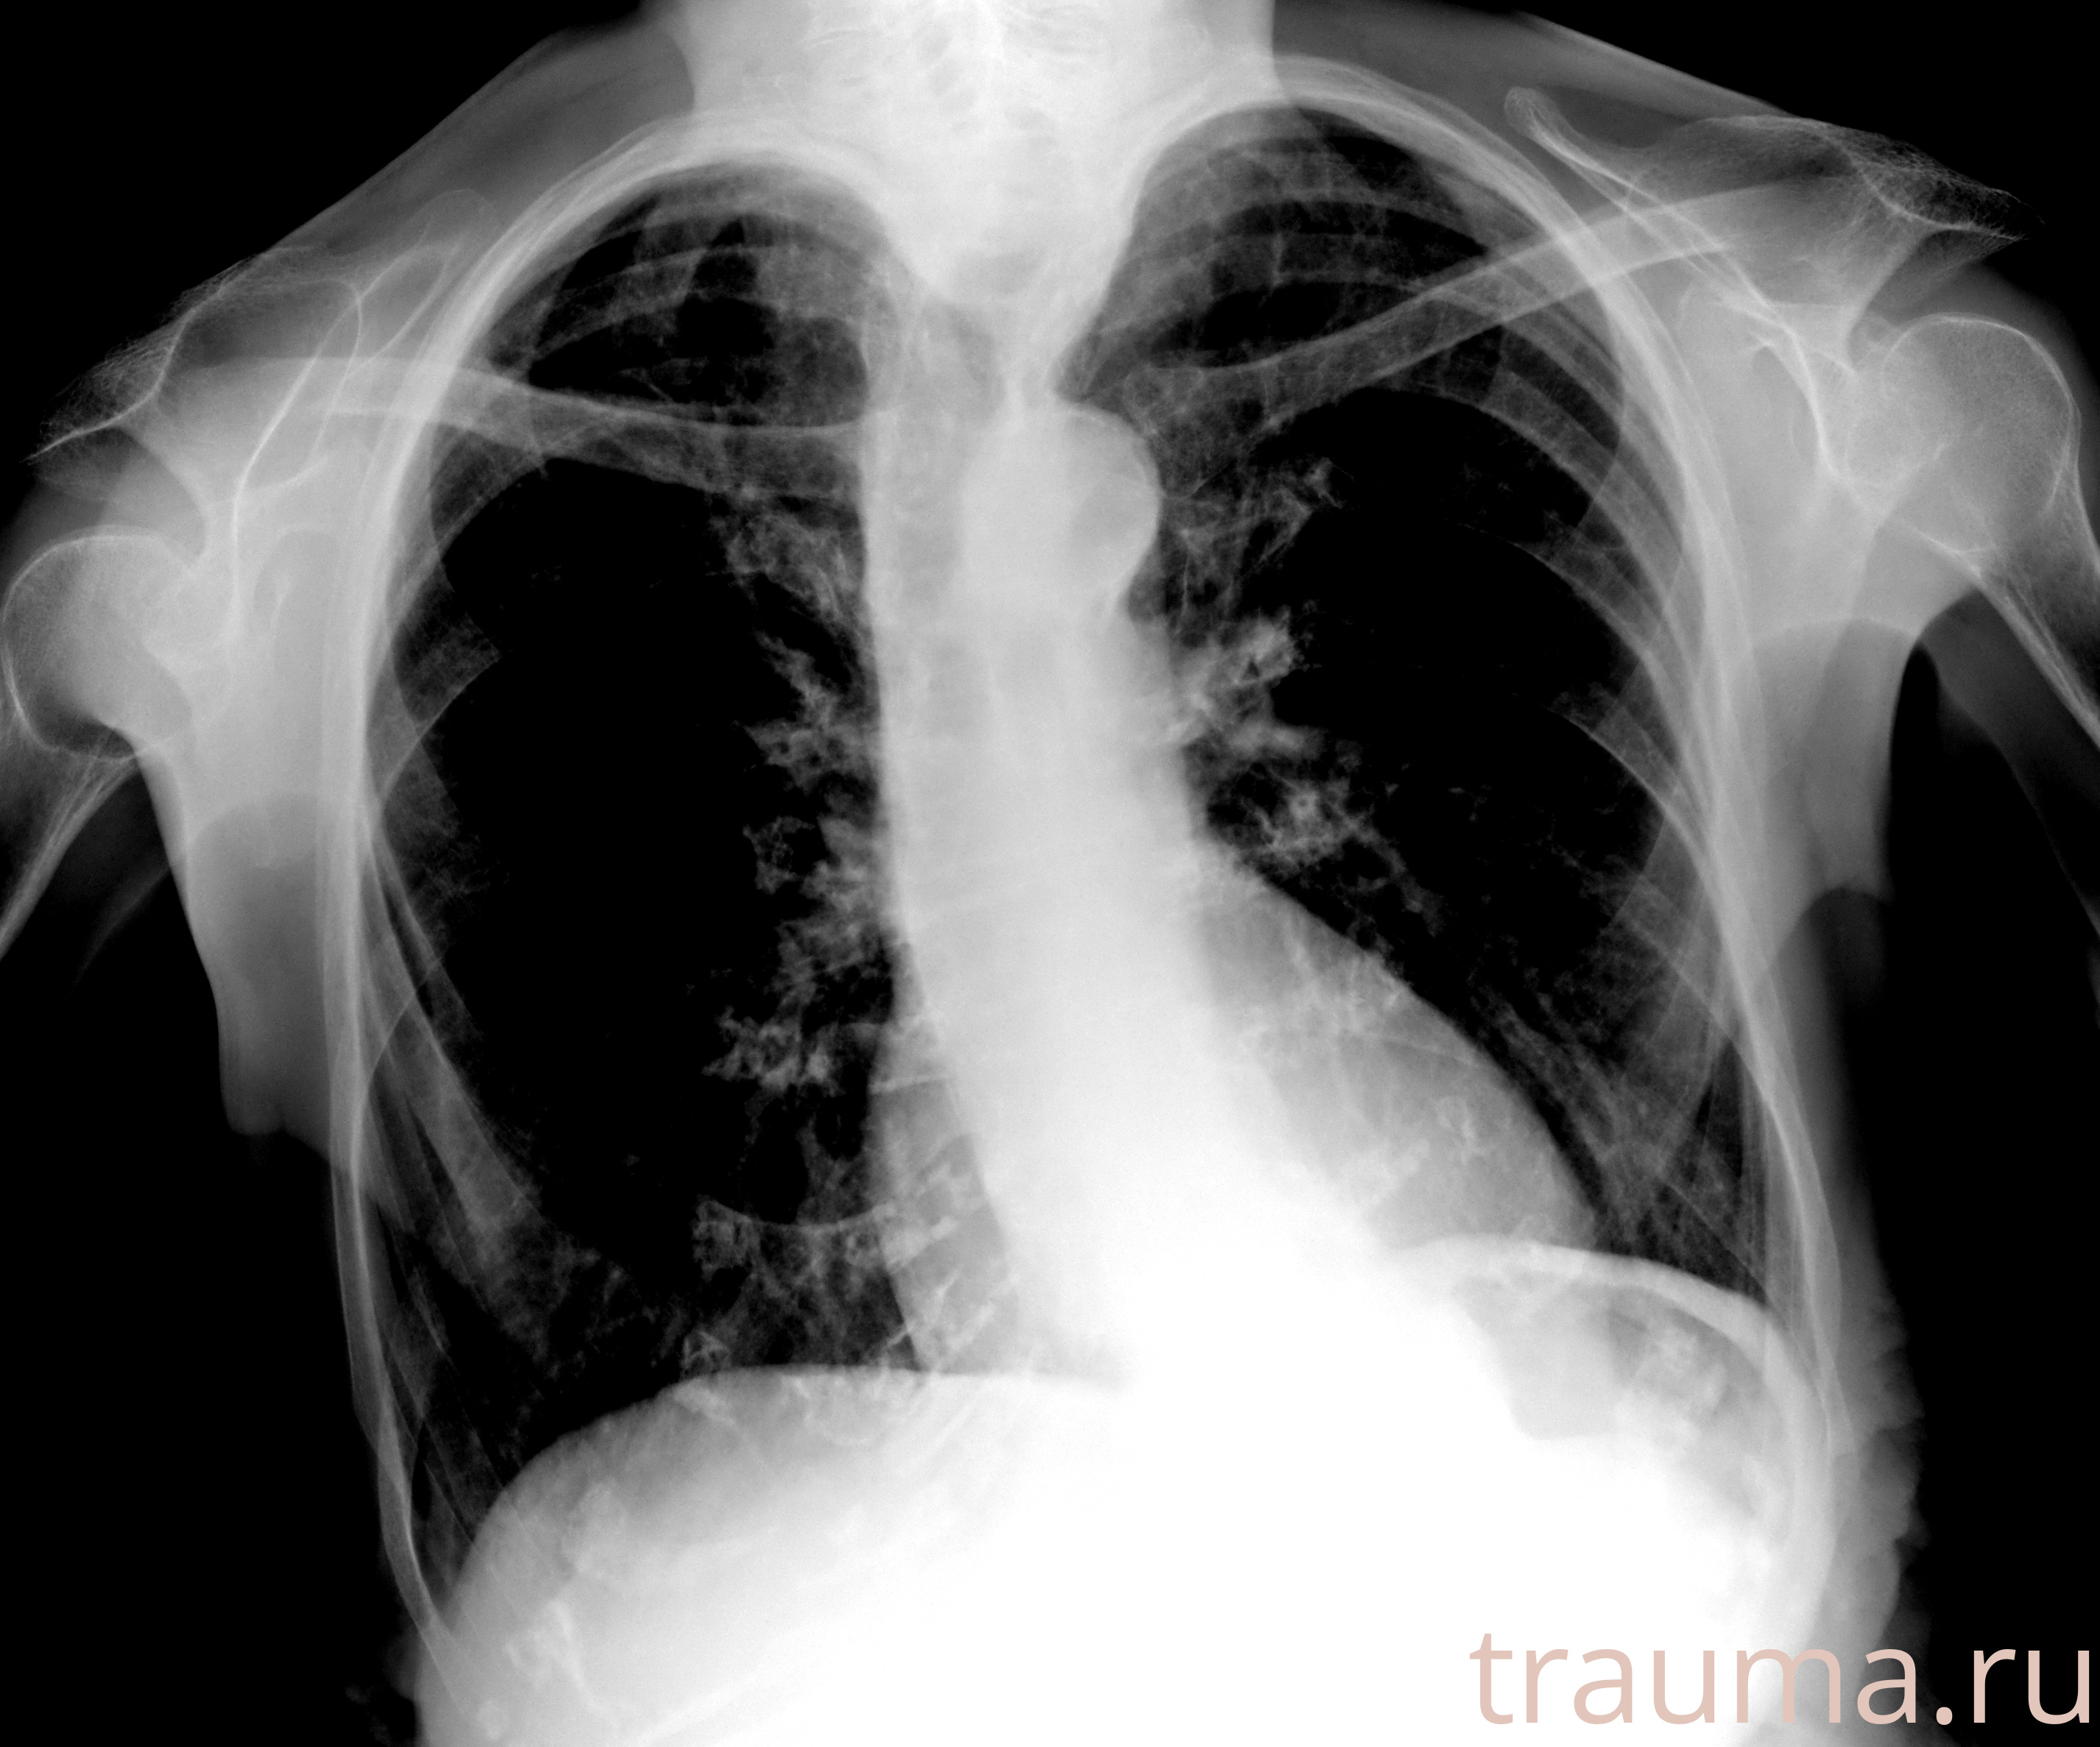

Рентгенограммы

Рентген на дому: по вашему адресу приезжает врач-рентгенолог, травматолог-ортопед с мобильным рентгеновским аппаратом, проводит диагностику травмы или заболевания, делает необходимые рентгенограммы, дает рекомендации по дальнейшему лечению. Получить качественные снимки в домашних условиях возможно благодаря уникальной методике, разработанной МосРентген Центром для института  Склифосовского